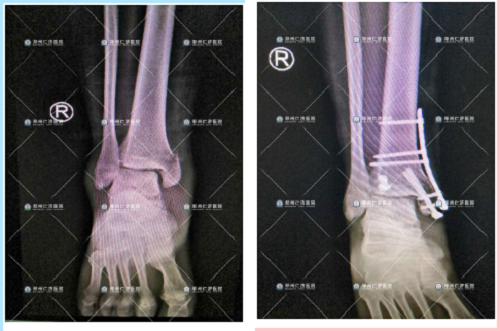

取内固定前、后

第一次治疗前、手术后,恢复良好

历时近4个小时,谷国俊副主任带领团队成功为其进行了右内踝部粉碎性骨折并神经损伤、右后踝骨折切开复位内固定术,术后转入病房给予精细观察和治疗。

谷国俊副主任说,“因为是粉碎性骨折,术中需要将每一块碎了的骨骼面精准对齐,这样才能保障康复后的效果,因为是粉碎性骨折,碎的块数比较多,无疑就增加了手术的难度”。